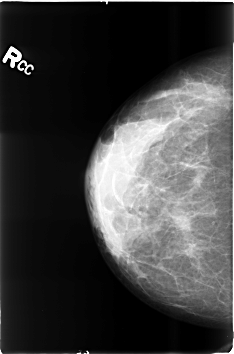

ics_version 1.0 filename B-3497-1 DATE_OF_STUDY 20 5 1998 PATIENT_AGE 38 FILM FILM_TYPE REGULAR DENSITY 3 DATE_DIGITIZED 8 6 1999 DIGITIZER LUMISYS LASER SEQUENCE LEFT_CC LINES 4624 PIXELS_PER_LINE 3056 BITS_PER_PIXEL 12 RESOLUTION 50 OVERLAY LEFT_MLO LINES 4640 PIXELS_PER_LINE 3072 BITS_PER_PIXEL 12 RESOLUTION 50 OVERLAY RIGHT_CC LINES 4600 PIXELS_PER_LINE 3032 BITS_PER_PIXEL 12 RESOLUTION 50 NON_OVERLAY RIGHT_MLO LINES 4600 PIXELS_PER_LINE 3008 BITS_PER_PIXEL 12 RESOLUTION 50 NON_OVERLAY |